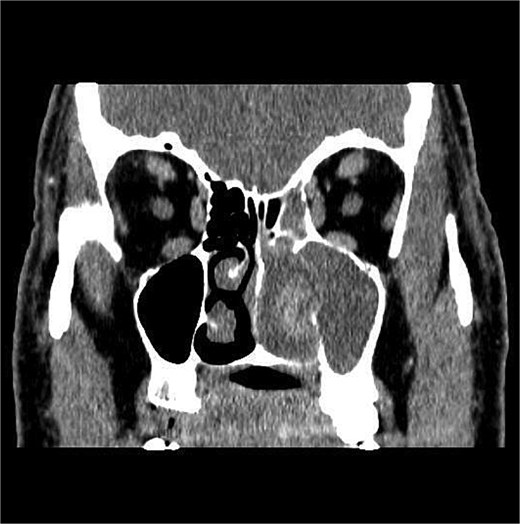

CT showed a heterogeneously enhancing mass completely occluding the left nasal cavity, left ethmoidal, maxillary and frontal sinuses, extending to left pterygopalatine fossa. It is associated with bony erosion of the posterior nasal septum and the left medial maxillary wall (Figs 1 and 2). Findings were suggestive of inverted papilloma vs sinonasal malignancy. Therefore, biopsy was recommended.

Coronal section of CT paranasal sinus with contrast soft tissue window showing the mass occupying the left nasal cavity and extending to maxillary and ethmoidal sinus.